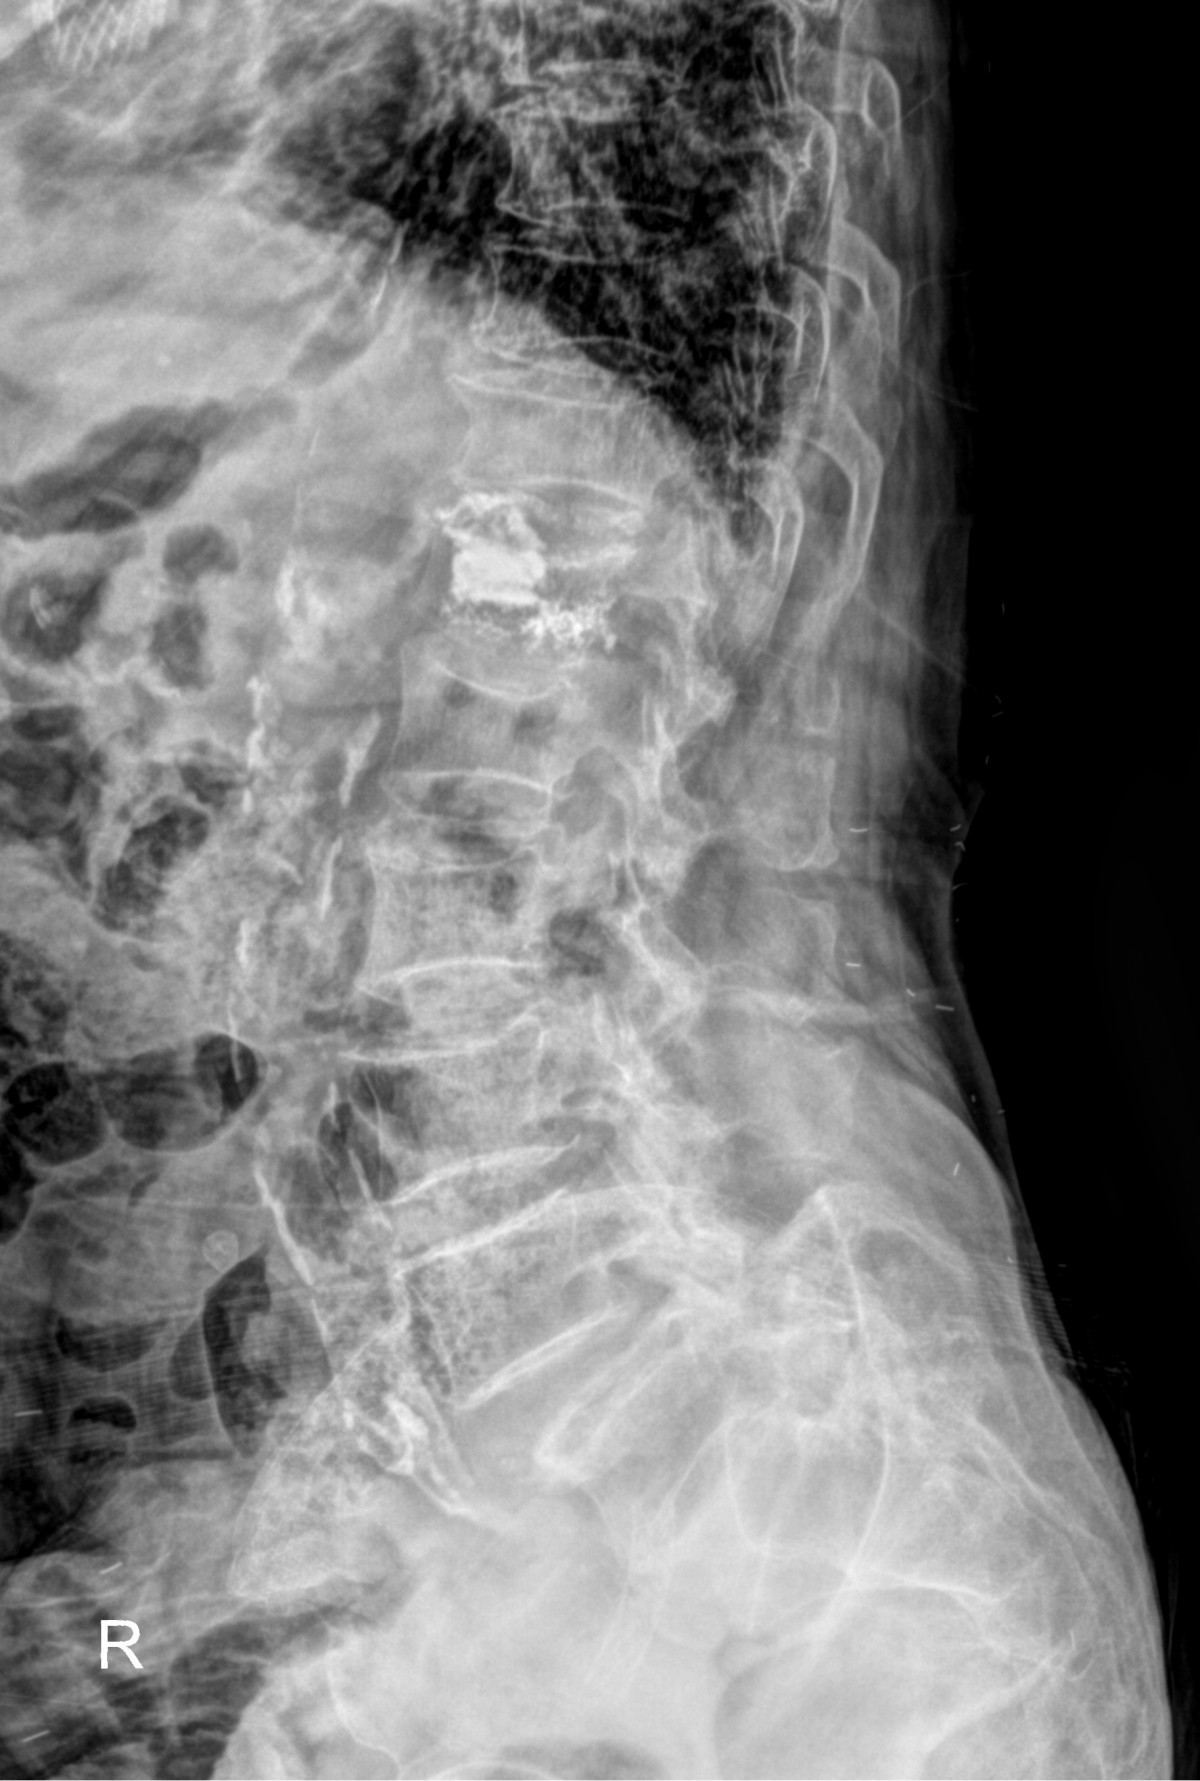

정지영원장님 허리 골절 골시멘트 성형술 김재O 환자

dae765e4d9ac96aee867c9d6292d8784_1758007819_598.jpg